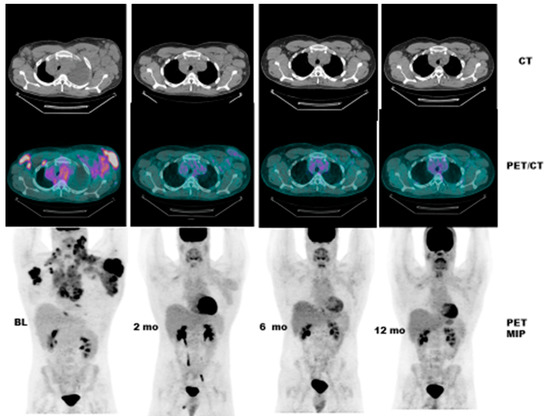

- Case # 3:

- This is a 46 year old female with recurrent GIST. She had multiple prior therapies including imatinib, sunitinib, regorafenib, nilotinib, and pazopanib. After 2 weeks of new therapy with a novel TKI targeting c-KIT, she had a complete metabolic response, but only a partial anatomic response. This showcases early response can be seen as early as 2 weeks in GIST another sarcoma like Ewing’s sarcoma where in early responses as early as 9 days have been shown to predict survival [38] (Figure 4).